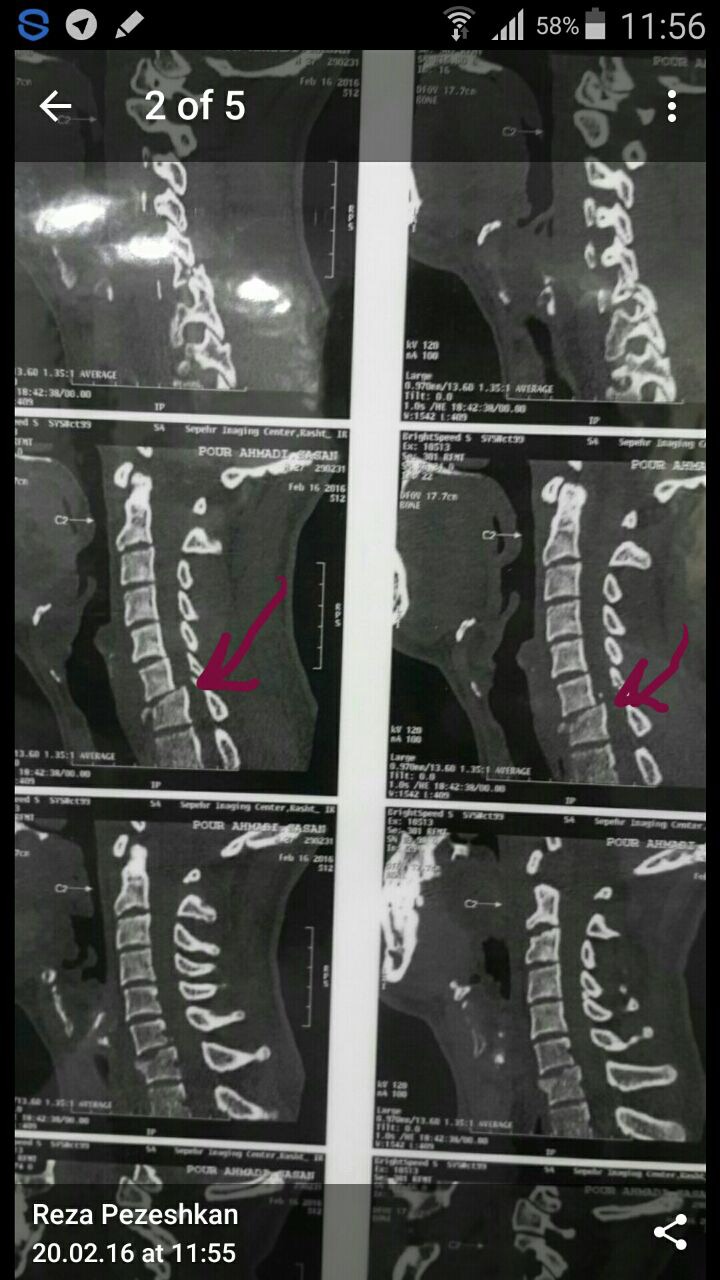

بیمار جهت بررسی بیشتر به بیمارستان شهید بهشتی بندرانزلی اعزام شد که بلافاصله برای بیمار CT فقرات سرویکال و نیز MRI در خواست شد.

شکستگی مهره C7گردنی همراه با درگیری کانال نخاعی وجود داشت که در صورت عدم جراحی سریع می توانست باعث فلج هر4 اندام بیمار شود.